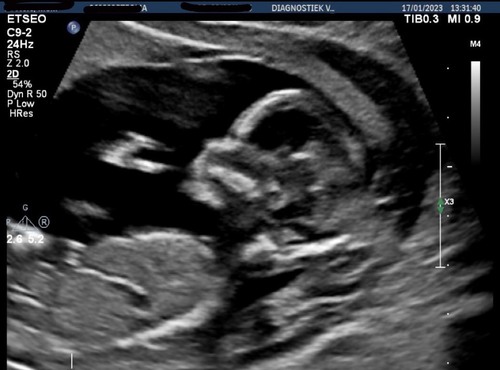

Iemand hier een idee ( vorige topic werd helaas gesloten. Mijn vrouw is 12+4 weken hieronder)